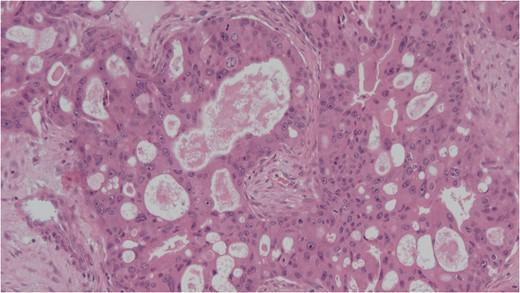

Histology of the mass confirmed sinonasal SDC. Tissue specimens showed cellular stroma extensively infiltrated by carcinoma composed of large eosinophilic cells with gland formation (Fig. 2). Widespread nuclear pleomorphism was evident. The sample was positive for cytokeratin-7 (CK7) (Fig. 3), epithelial membrane antigen (EMA), BerEP4 and demonstrated focal positivity for cytokeratin-5/6 (CK5/6). Post-operative MRI scans were requested to rule out residual disease or cervical lymphadenopathy (Fig. 4). Following review by Regional Head and Neck Cancer multi-disciplinary team and the oncologist, the patient was treated with a radical course of radiotherapy which was completed without complications. The patient has been reviewed regularly in the Head and Neck Cancer clinic with no evidence of recurrence at 18 months.

Cellular stroma extensively infiltrated by carcinoma composed of large eosinophilic cells with gland formation on medium power view. Haemotoxylin and eosin (H&E).